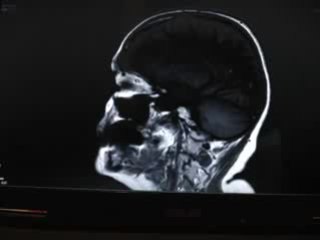

La tumeur au cerveau de cette femme était en fait un ver vivant